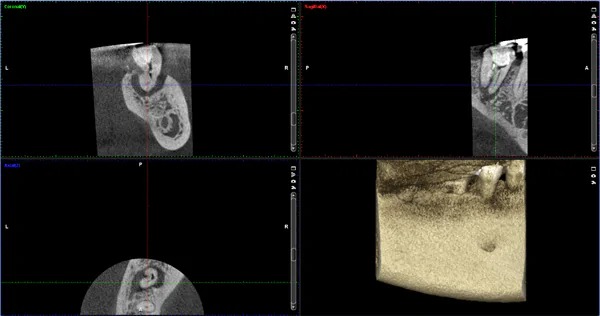

歯科用CT

従来のレントゲン写真では、歯と周りの骨を2次元でしか把握できませんでしたが、CT画像では3次元的に状態を把握することが可能になりました。これにより、診断と治療の質を高めることが可能になりました。

- レントゲンやCTを用いて正確に診断をする事